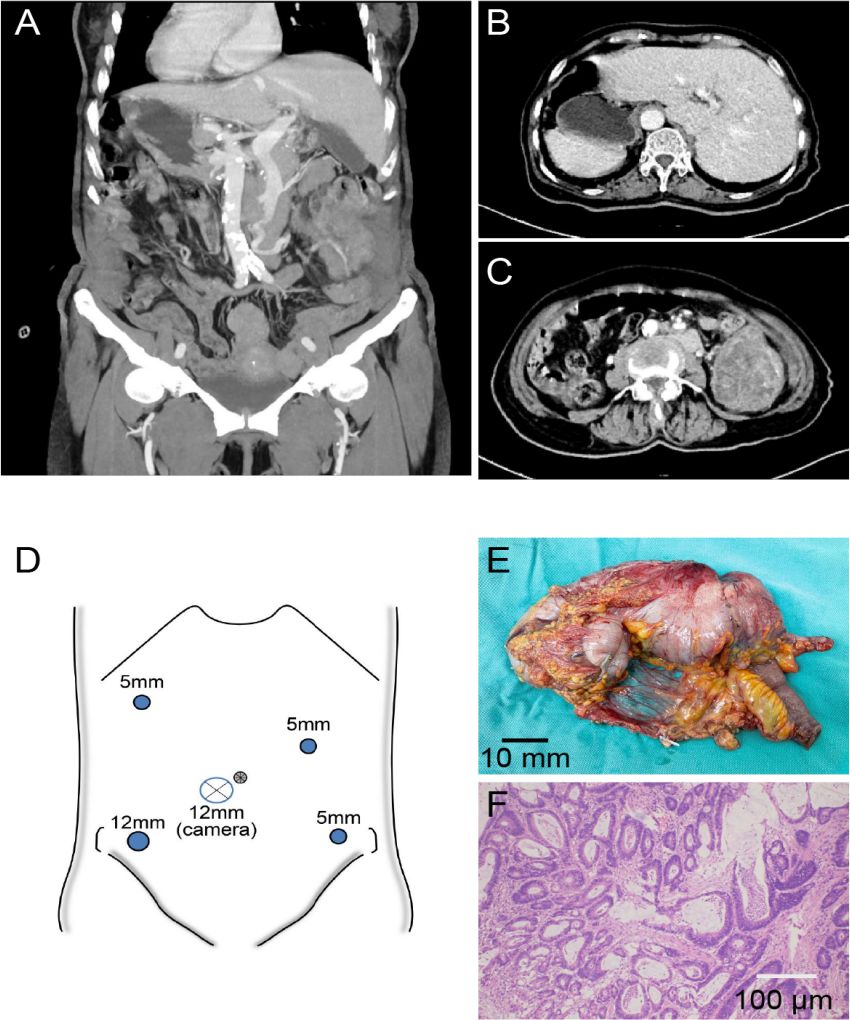

Background:Our patient exhibited situs inversus totalis (SIT) – a developmental quirk resulting in right-left transposition of all visceral organs, including the heart, liver, and spleen. While prior case reports have described colorectal carcinoma in individuals with SIT, to our knowledge, this case represents an exceptionally rare presentation of primary cecal carcinoma within this anatomical context. This case describes a patient undergoing laparoscopic right hemicolectomy for adenocarcinoma of the cecum. Case presentation: A patient presented to our institution in May 2024. Subsequent diagnostic workup confirmed a diagnosis of cecal carcinoma. Given the absolute contraindication for bowel preparation secondary to complete bowel obstruction, along with radiologically confirmed cecal malignancy and elevated serum tumor markers, a multidisciplinary consensus was reached to proceed with laparoscopic right hemicolectomy after obtaining proper informed consent from the patient's family.Pathology confirmed a T3N0M0 well-differentiated adenocarcinoma. Twelve-month consecutive postoperative follow-up data confirmed the absence of surgical complications such as anastomotic leakage or infection, as well as no clinical or radiographic evidence of disease recurrence. Conclusions:Although the reversed anatomy in SIT patients presents inherent technical challenges for laparoscopic surgery, this minimally invasive approach can still achieve comparable safety and efficacy to conventional procedures when performed by experienced surgeons with adequate anatomical understanding.